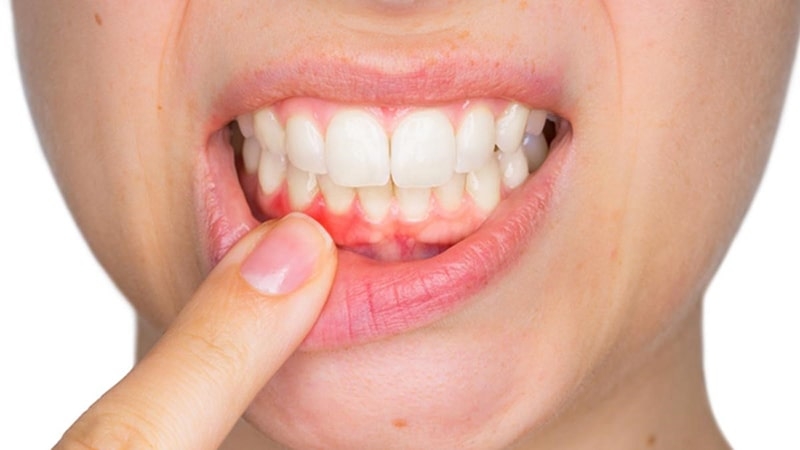

Các triệu chứng phổ biến nhất của viêm lợi bao gồm: Lợi đỏ sưng lên, chảy máu chân răng, hôi miệng, ngứa và đau lợi. Nếu không điều trị kịp thời dễ dẫn đến viêm lợi có mủ và gây hại cho thai nhi.

Cách chữa viêm lợi cho bà bầu không gây tác dụng phụ 3Tìm kiếm cách chữa cho bà bầu phù hợp để giảm tình trạng sưng viêm gây đau nhức khó chịu